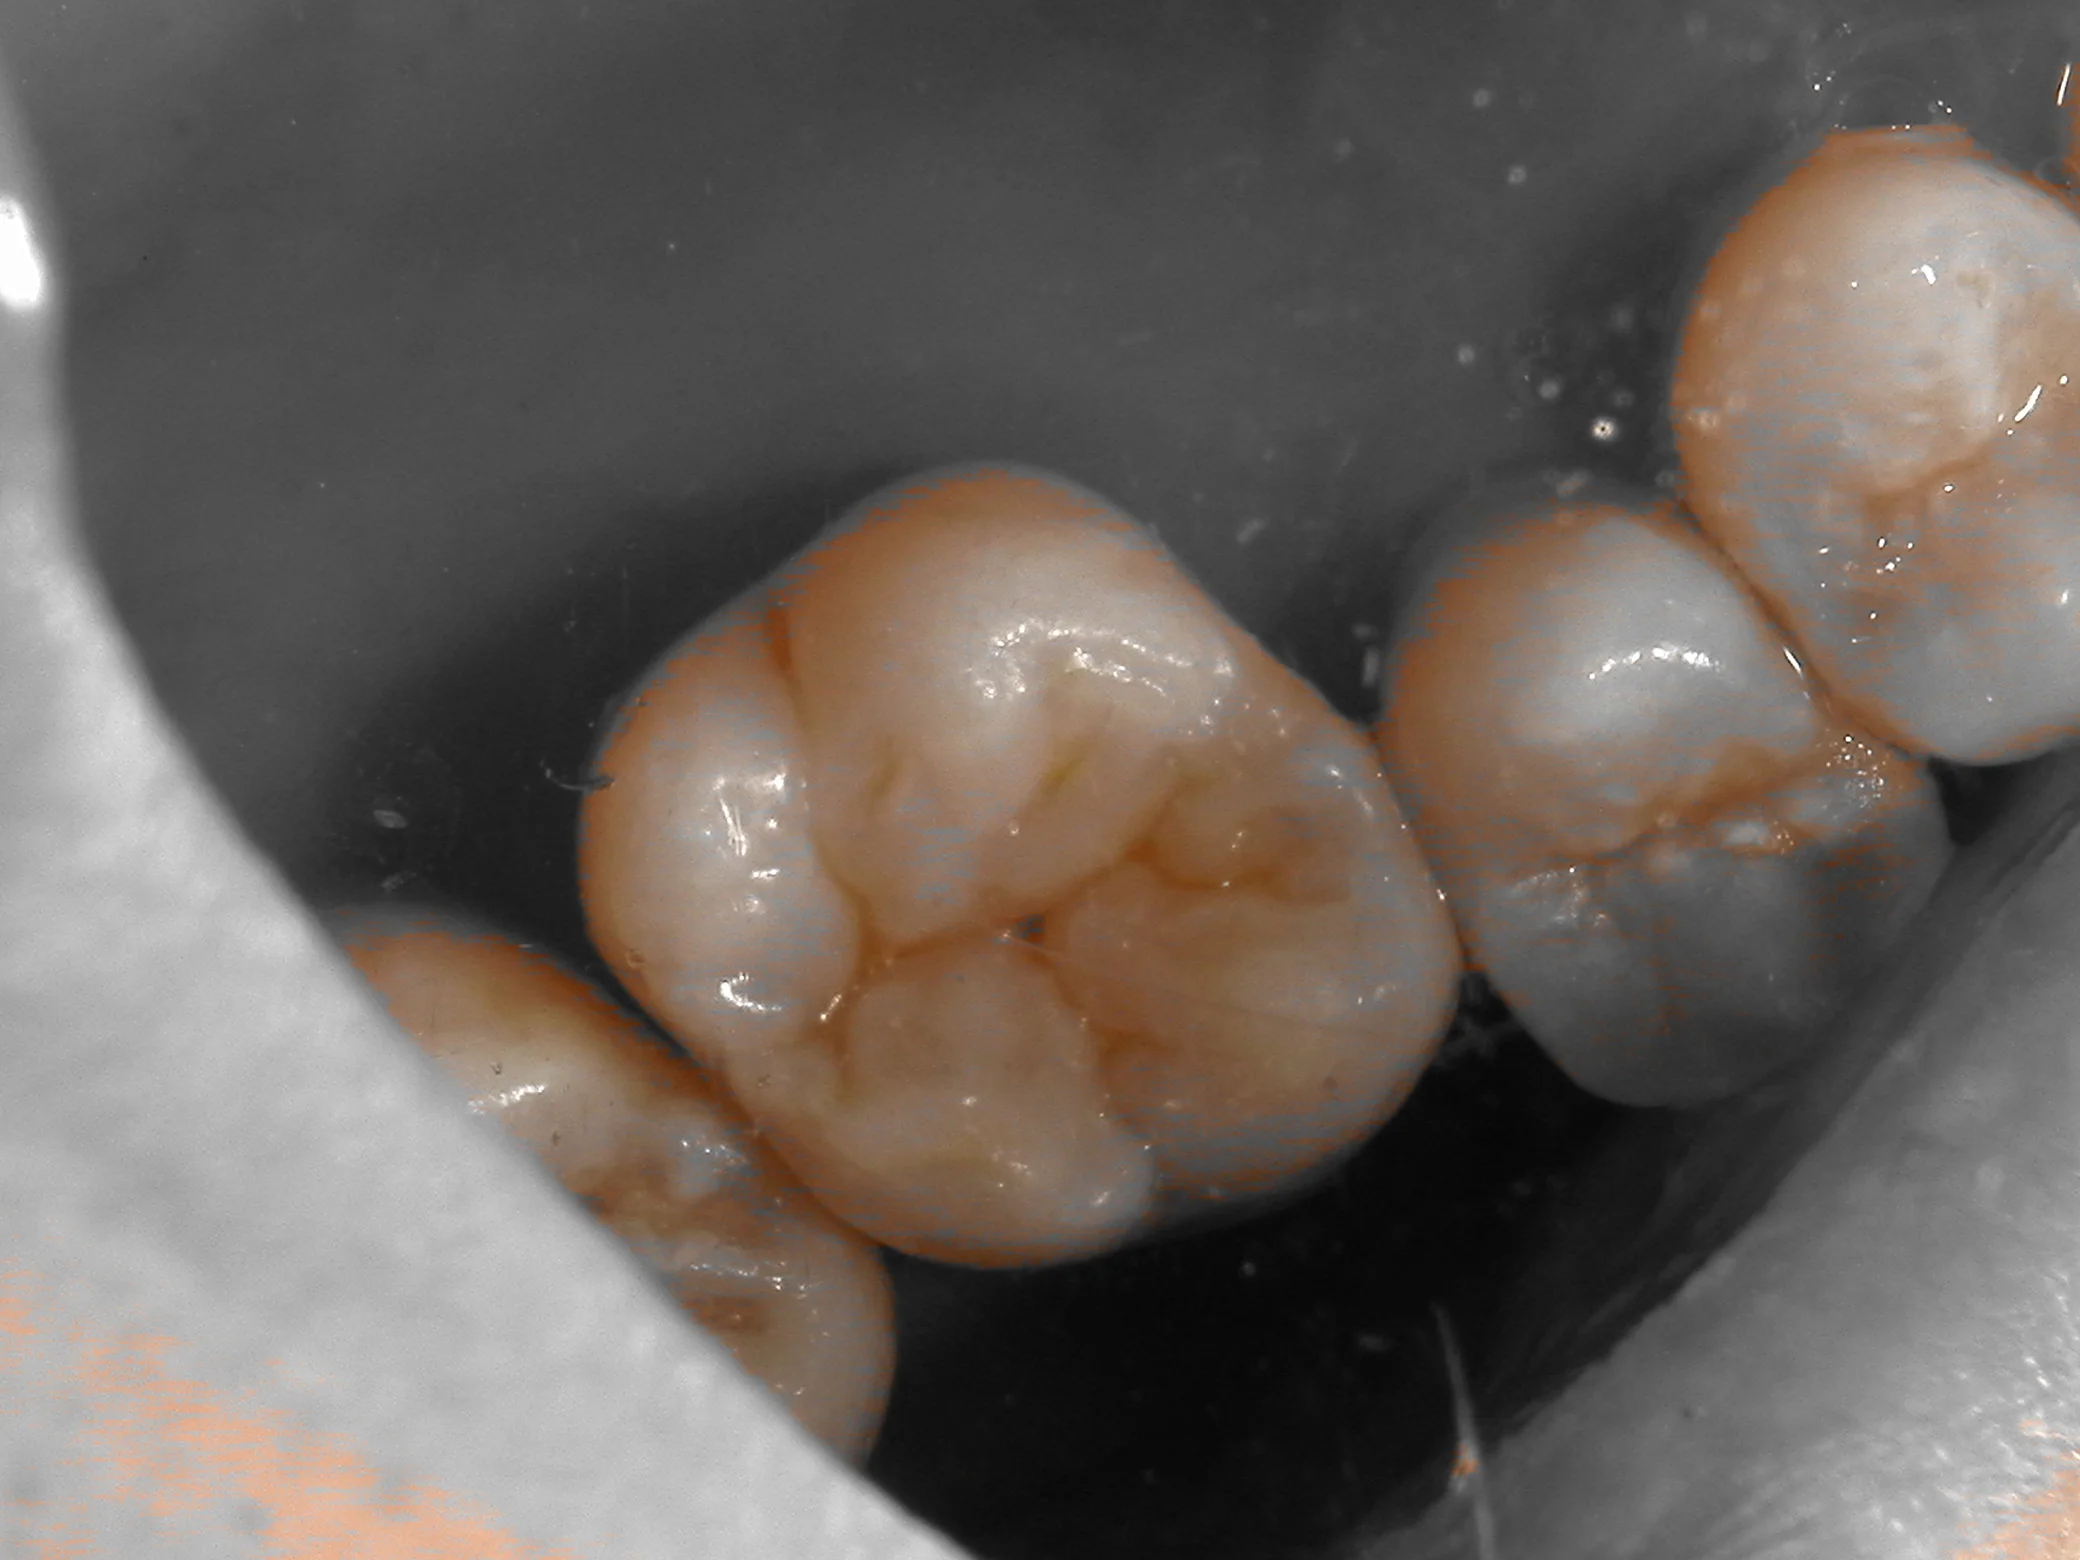

まず、普通の状態。

そして、色の違いを分かりやすくするためのシェード抽出画像。

どうでしょうか?

若干、中心裂溝(中央の黒い点)の深さを深くしすぎてしまった感じはありますが・・・

そこまで大きな色の違いは出ていないと思います。